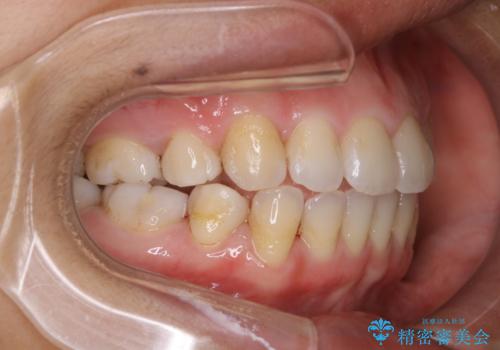

タバコをよく吸う方で1年ぶりのクリーニングになるそう。ただ、昔から着色が付きやすく取れないとのこと。

エアフローを使いましたが、汚れはとても頑固で、元々歯の面に多くの凹凸があり、その隙間に入り込んでいる着色、虫歯の初期による変色以外を除去していきました。60分でも時間は足りませんでした。